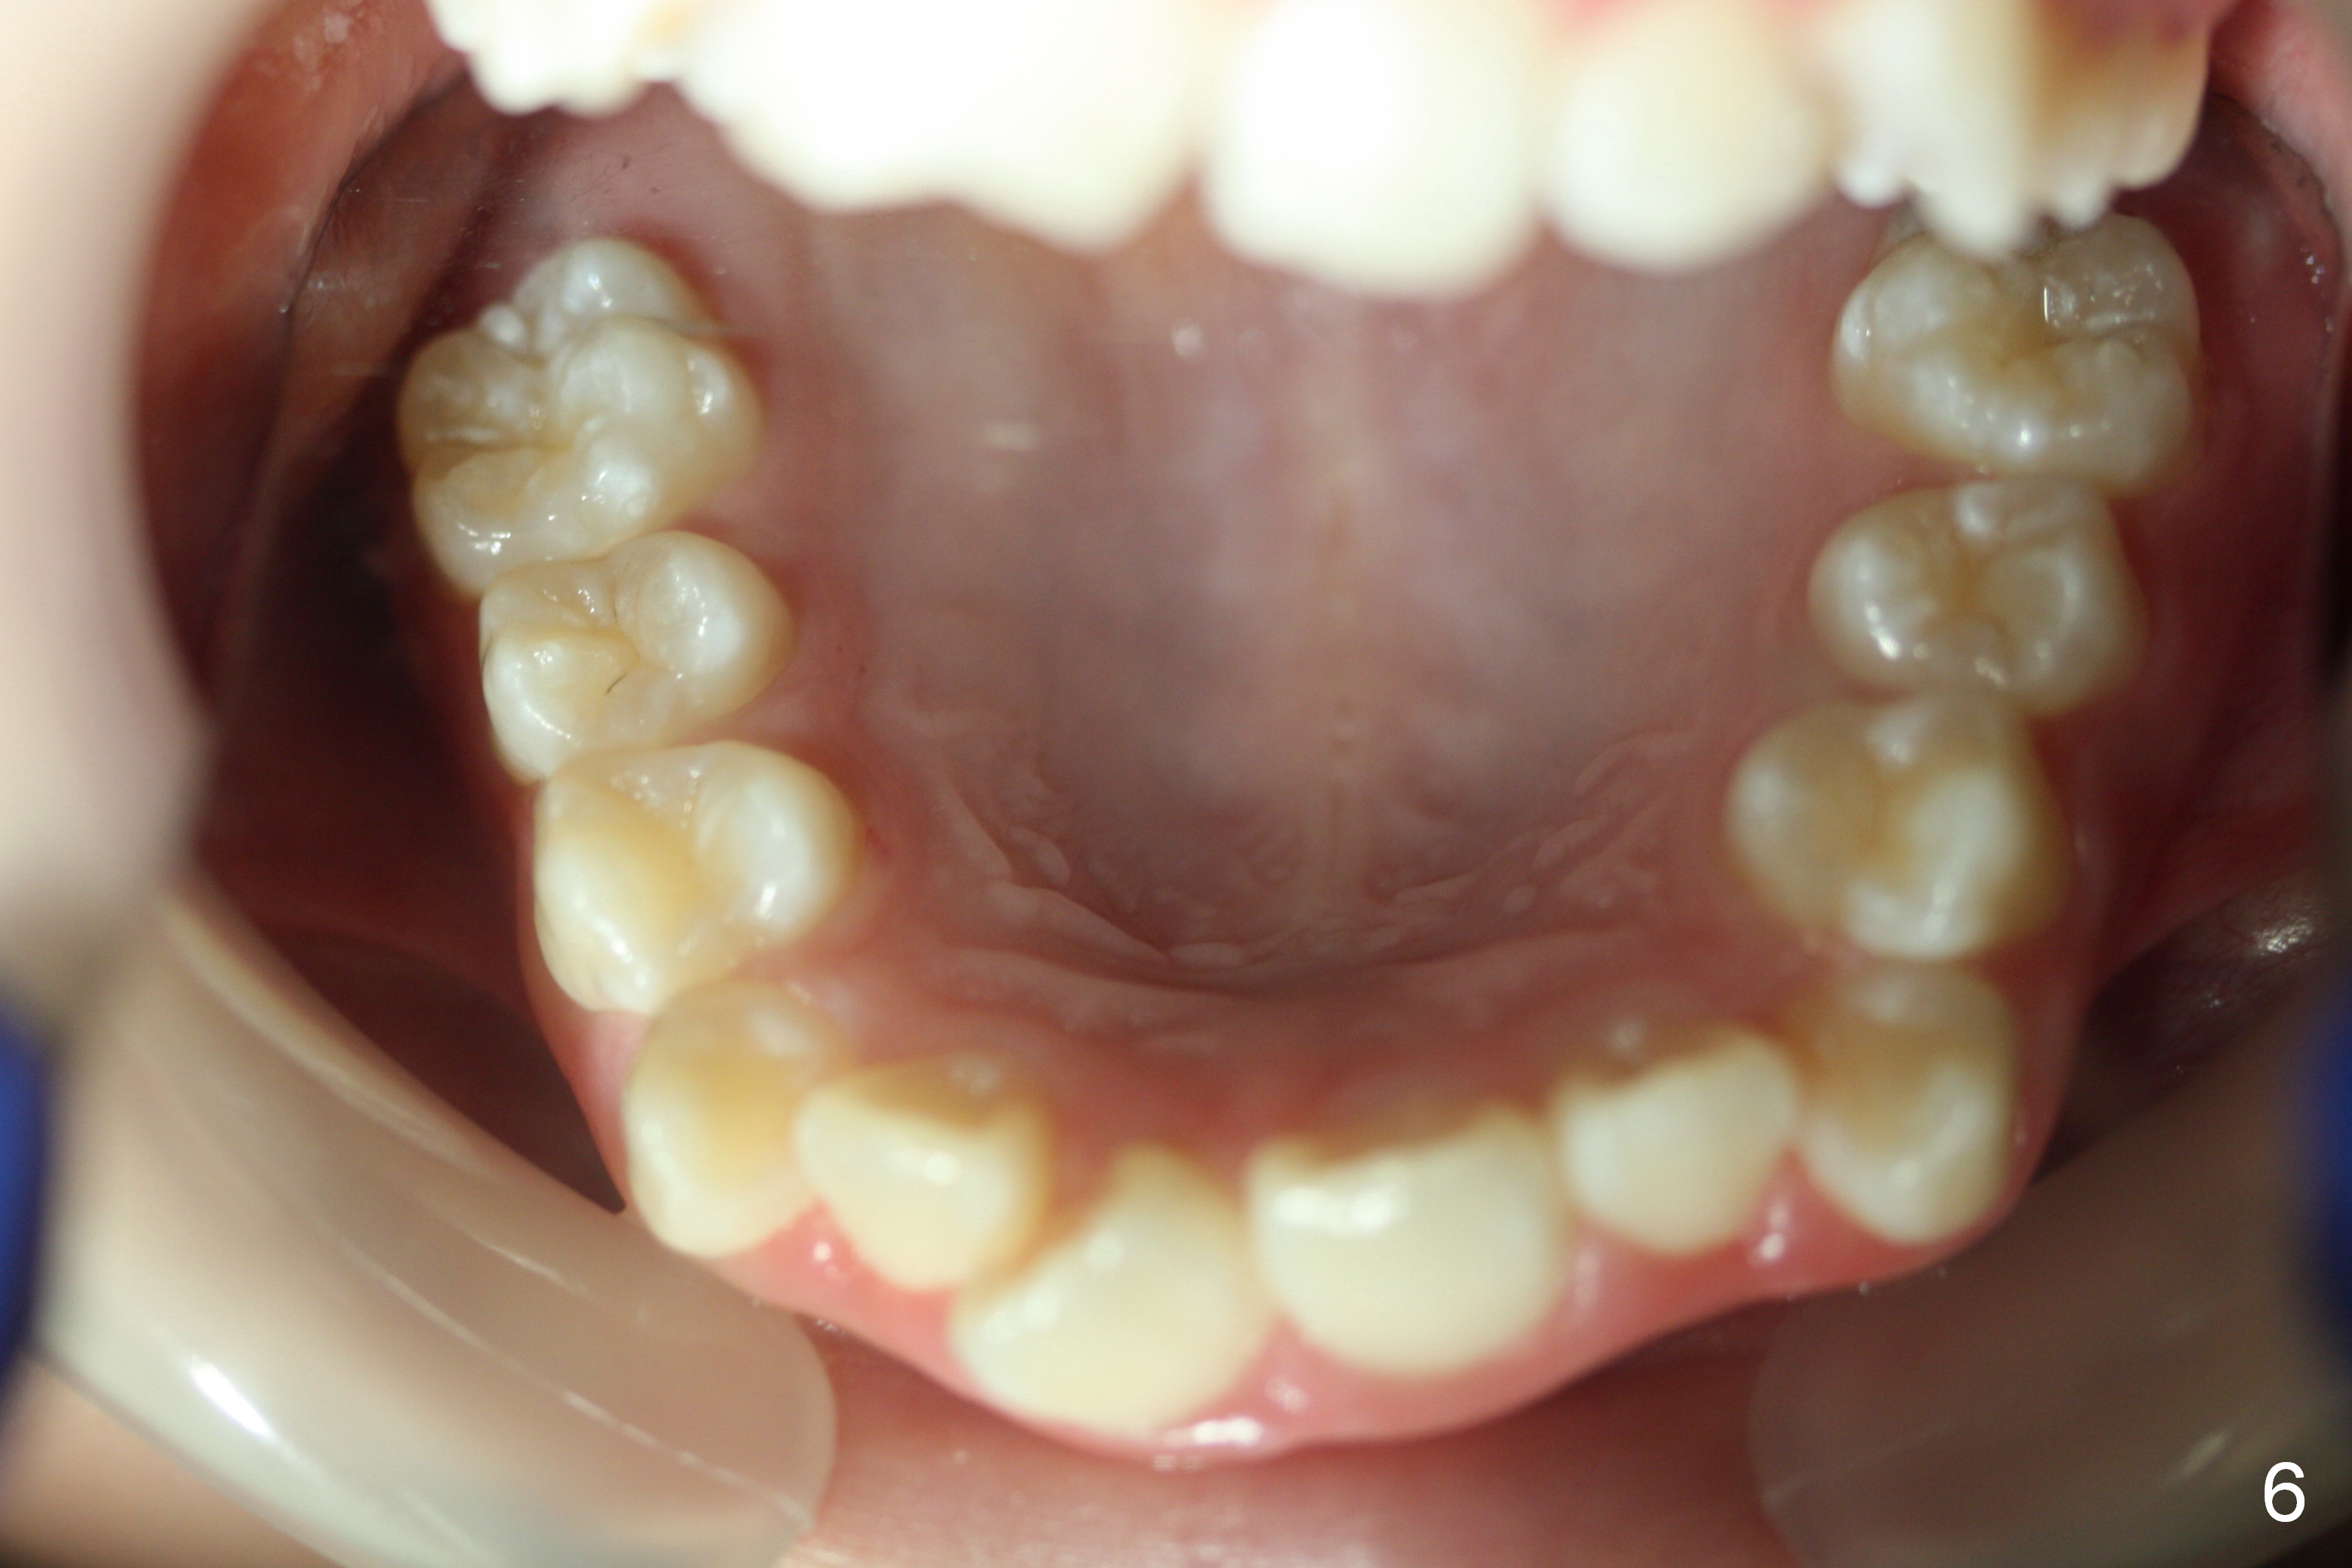

A 13-year-old girl presents for orthodontic consultation.  Chief complaint is crooked teeth.  Her brother is finishing 4 extraction ortho.

Looking at the records, the lower incisors are protrusive and have crowding, so think extraction.  There is enough combined crowding and class II to warrant extraction.  Since there is lower crowding, it would be 4 bicuspid extractions with the sliding mechanics using elastics or Niti closing coil springs. Closing the extraction space by maintaining the lower incisor position and moving the lower molars forward.  The upper arch is 50/50 front going back/back coming forward. Dr. Doug Ness, March 13, 2015 1:18 AM